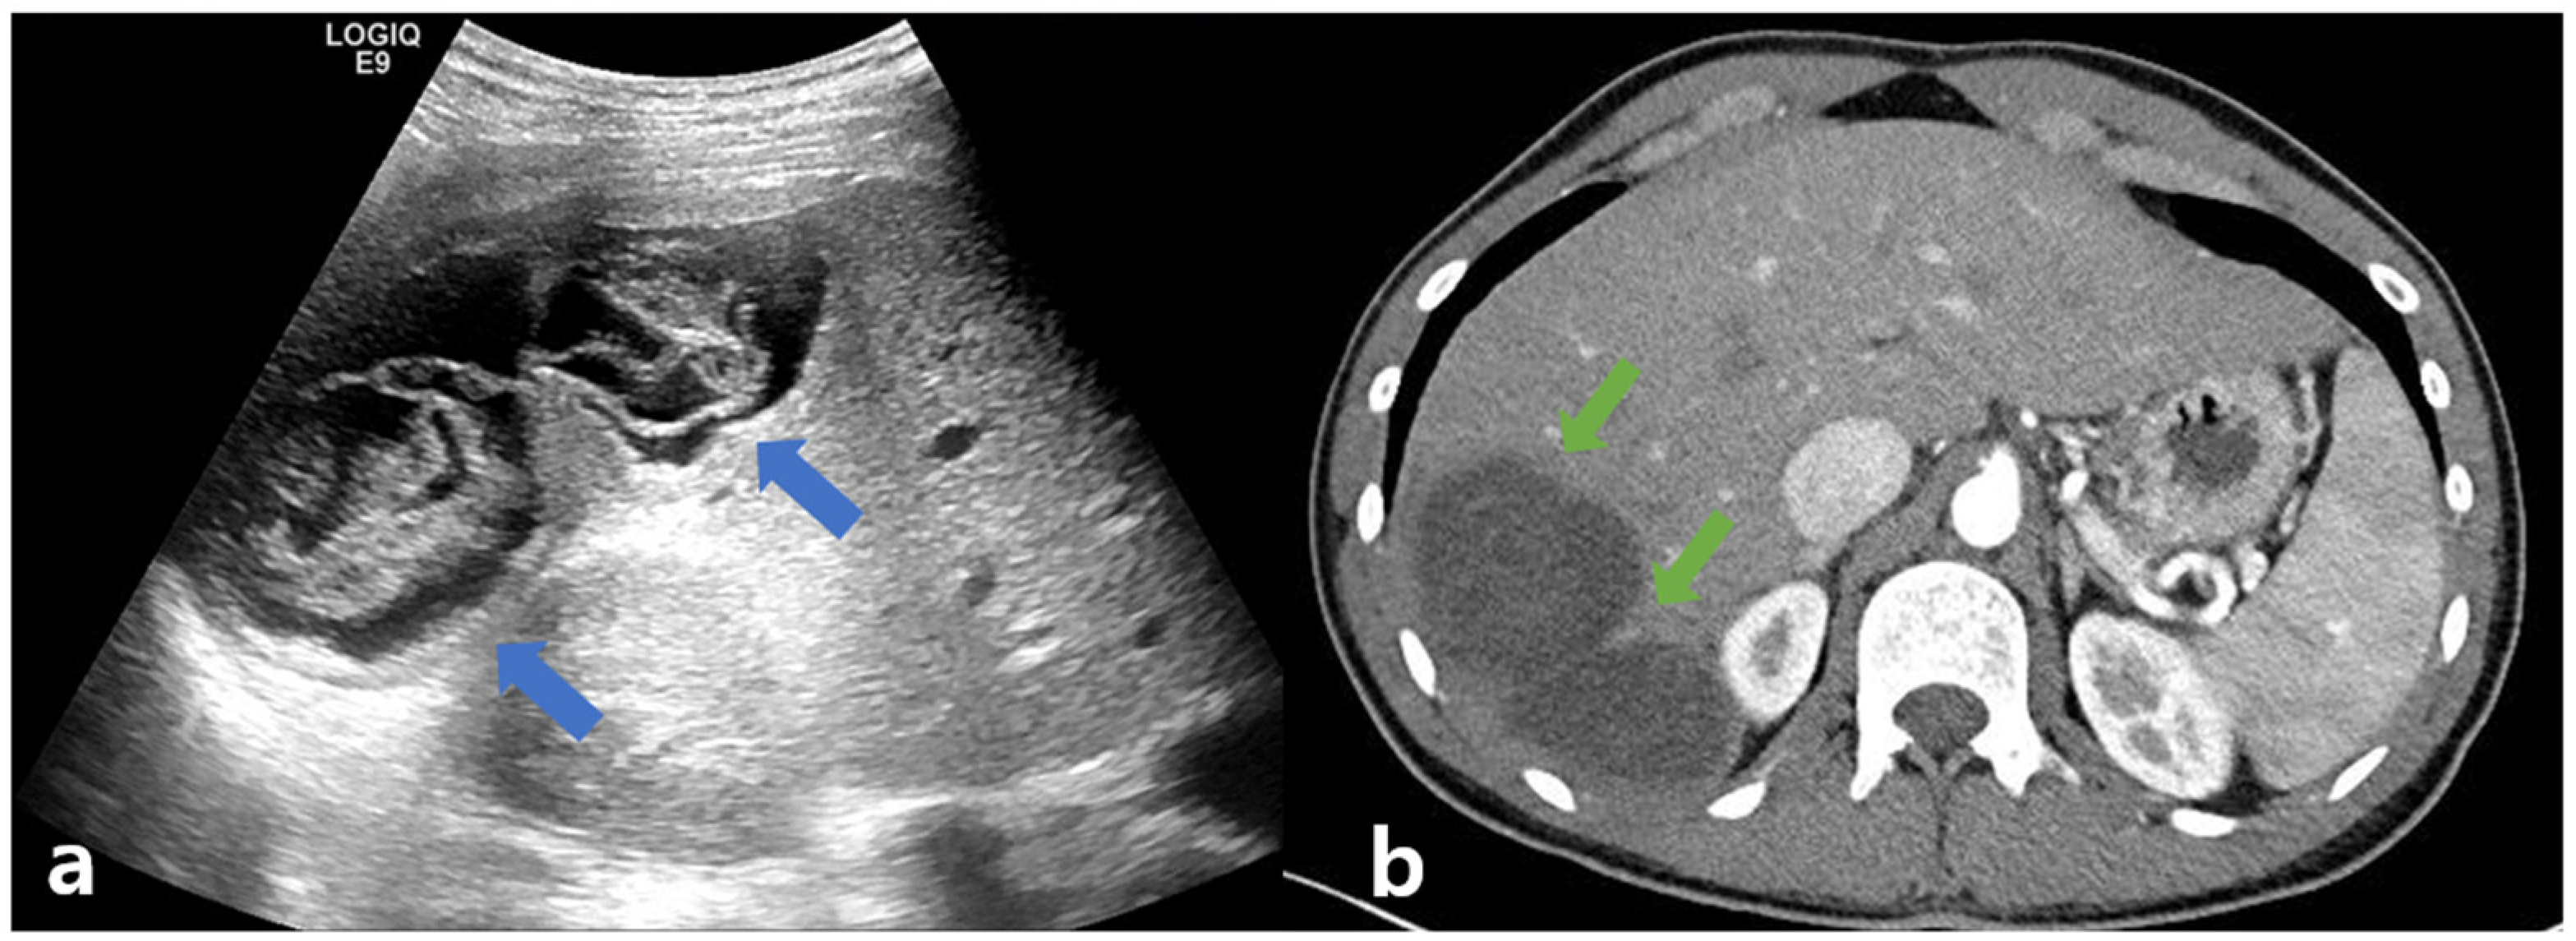

A 23-year-old man, who presented with dyspepsia and intermittent right upper quadrant pain for several weeks, was transferred to a tertiary hospital because of the abnormal findings on CT, including a septal low-density lesion. He was 71.8 kg in weight, 181cm tall, and had a body mass index of 21.92. He had no previous history of taking medications or alcohol and no relevant medical history. He was a foreign worker from Uzbekistan who had migrated 3 years prior, and he was not trying to recall if he had ever interacted with livestock or pets. He claimed to have lived in the urban city and was a student while in Uzbekistan. Currently, he is working at mechanical parts factories, less relevant for parasites. For further evaluation, laboratory examinations, including liver function tests, parasite analysis, and hepatobiliary sonography, were performed. The results of the laboratory tests were as follows: white blood cell (WBC) count, 6560/μL; eosinophilia, 860 cells/μL (proportion of WBC, 13%); hemoglobin, 15 g/μL; platelet count, 200 K/μL; total protein, 7.82 g/dL; albumin, 4.47 g/dL; total bilirubin, 0.62 mg/dL; direct bilirubin, 0.23 mg/dL; aspartate aminotransferase (AST), 20 IU/L; alanine aminotransferase (ALT), 19 IU/L; alkaline phosphatase, 104 IU/L; gamma glutamyl transferase, 36 IU/L; blood urea nitrogen, 12.3 mg/dL; creatinine, 0.87 mg/dL; and international normalized ratio, 1.12. Serologic markers for viral hepatitis, including the hepatitis B virus surface antigen, hepatitis B virus core antibody, hepatitis B virus antigen, and hepatitis C virus antibody, were negative. The hepatitis B virus surface antibody was positive. The laboratory test for autoimmune hepatitis, such as the anti-nuclear antibody, smooth muscle antibody, liver kidney microsomal type 1 antibody, and antimitochondrial antibody, were also negative. Additional laboratory findings for parasites, including serum Toxocariasis, C. Sinensis, Cysticercosis, Paragonimus, Fasciola hepatica, and Sparganum immunoglobulin G (IgG), were performed. Of these, only the cysticercosis IgG test was positive. Abdominal ultrasonography showed two communicating, incomplete loculated anechoic lesions measuring approximately 8–11 cm and filled with folded linear echoic materials in liver segment 6. (Figure 1a) Abdominal computed tomography revealed two communicating hypodense cysts occupying a slightly enhancing material. (Figure 1b).

Figure 1.

Abdominal ultrasonography (a): two communicating, incomplete loculated anechoic lesions, measuring approximately 8–11 cm, filled with folded linear echoic materials (blue arrows). Abdominal computed tomography (b): two communicating hypodense cystic lesions, measuring approximately 8–11 cm, filled with slightly enhancing material (green arrow).